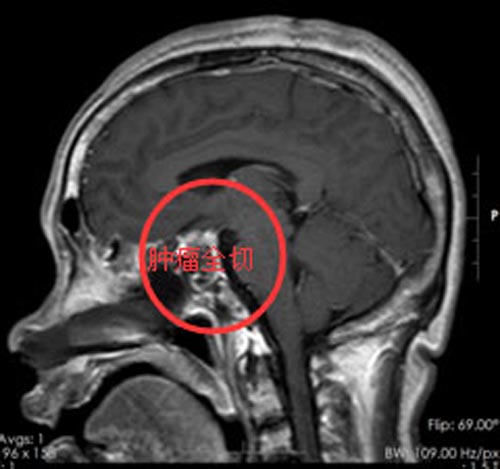

在家人的提醒下,张女士来到我院,头颅MR检查提示:“鞍区占位性病变,考虑垂体大腺瘤可能”;内分泌检查提示生长激素和垂体催乳素都过高,属于垂体瘤中的激素分泌异常症群。她终于清楚了自己“变脸”的原因。

完善相关术前检查后,张女士在垂体瘤诊疗中心行“内镜经鼻蝶鞍区垂体大腺瘤切除术+颅底重建术”,手术顺利,术后复查激素水平已恢复正常。

▲手术前